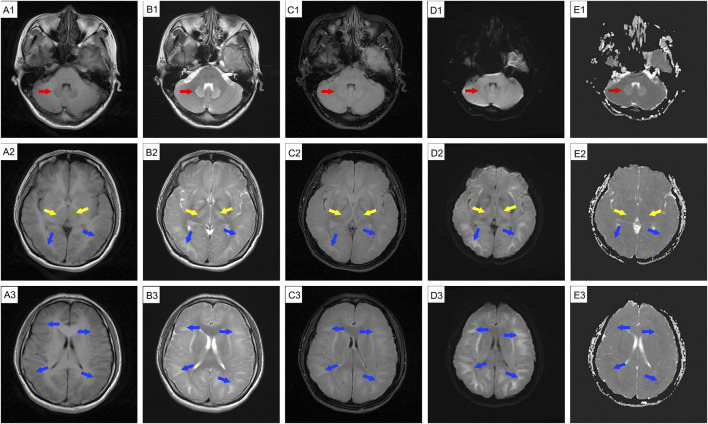

背景:1,2-二氯乙烷是一种常用的工业溶剂。急性或亚急性职业性接触可引起中毒性脑病;然而,脑成像的长期变化并不经常被记录下来。病例介绍:一名39岁女性在涂胶9天后出现头晕和健忘。休息7天后,她的症状明显好转。然而,恢复工作3天后,她返回时出现头晕、头痛和焦虑。脑磁共振成像(MRI)显示小脑齿状核、基底节区和双侧脑白质广泛水肿和弥漫性异常信号。给予丹参酚酸注射液、异甘草酸镁及神经营养治疗。入院两周后,除轻度行走不协调外,患者症状明显改善。异常MRI信号的范围与先前的发现一致。她第二天就出院了。3天后头痛加重。计算机断层扫描显示弥漫性脑水肿。尽管用甘露醇治疗,她的头痛迅速恶化,并伴有恶心、呕吐、高血压、心动过缓和呼吸困难,最终导致昏迷。后续MRI显示与前次扫描相似,只是表观扩散系数(ADC)序列由低信号变为高信号。核磁共振检查后不久,她出现呼吸骤停。不幸的是,由于严重的脑损伤和感染,她在初次入院32天后死亡。结论:职业性暴露于1,2-二氯乙烷可导致中毒性脑病,表现为弥漫性进行性脑水肿。该病例表明,脑成像结果可能并不总是与患者的临床状况相关,因此仔细监测是必不可少的。

Case presentation: A 39-year-old woman developed dizziness and forgetfulness 9 days after performing glue coating. Her symptoms improved significantly after a 7-day break from work. However, after resuming work for 3 days, she returned with dizziness, headache, and anxiety. Brain magnetic resonance imaging (MRI) showed extensive edema and diffuse abnormal signal intensities in the cerebellar dentate nucleus, basal ganglia, and bilateral cerebral white matter. She was treated with salvianolate injection, magnesium isoglycyrrhizinate, and neurotrophic therapy. Two weeks after admission, her symptoms improved significantly, except for mild uncoordinated walking. The range of abnormal MRI signals remained consistent with previous findings. She was discharged the following day. She experienced worsened headache 3 days later. Computed tomography revealed diffuse cerebral edema. Despite treatment with mannitol, her headache rapidly worsened and was accompanied by nausea, vomiting, hypertension, bradycardia, and dyspnea, ultimately leading to unconsciousness. Follow-up MRI showed findings similar to the previous scan, except that the apparent diffusion coefficient (ADC) sequence had changed from hypointense to hyperintense. Shortly after the MRI examination, she experienced respiratory arrest. Unfortunately, she died 32 days after her initial admission due to severe cerebral injury and infection.